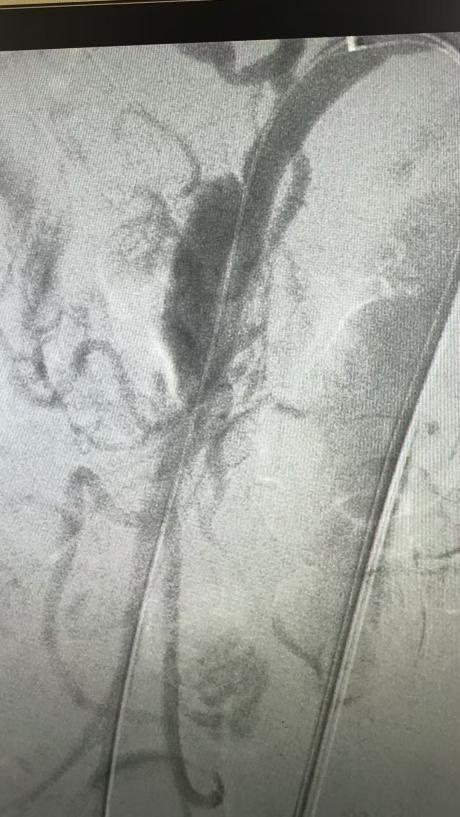

19:30,龚淞楠医生陪同患者及家属抵达嘉定院区急诊,并顺利完成交接。患者当时整体病情稳定,当晚入住血管外科,接受进一步评估和治疗。在排除相关禁忌后,11月4日,血管外科孙羽东副主任医师为患者实施了肠系膜上动脉夹层腔内隔绝+假腔栓塞术。